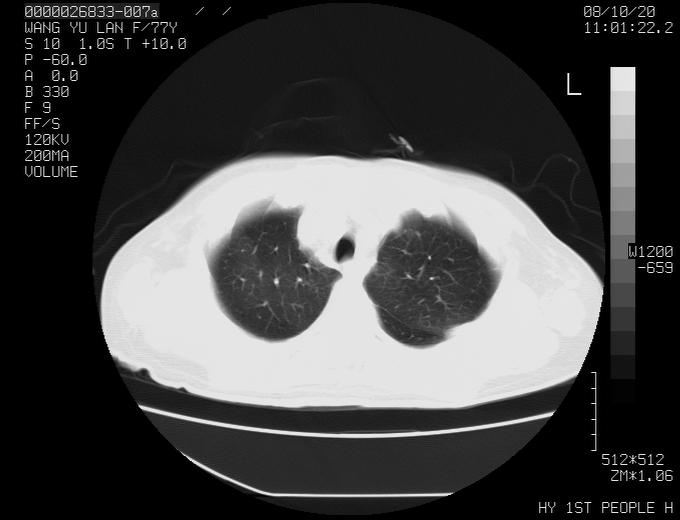

女性,77岁,胸部疼痛半月。左上肺团块影,本人考虑血管畸形,请分析

考虑肺癌

q我认为这么大的年齡,考虑周围型肺ca可能性大

考虑周围型肺ca可能性大